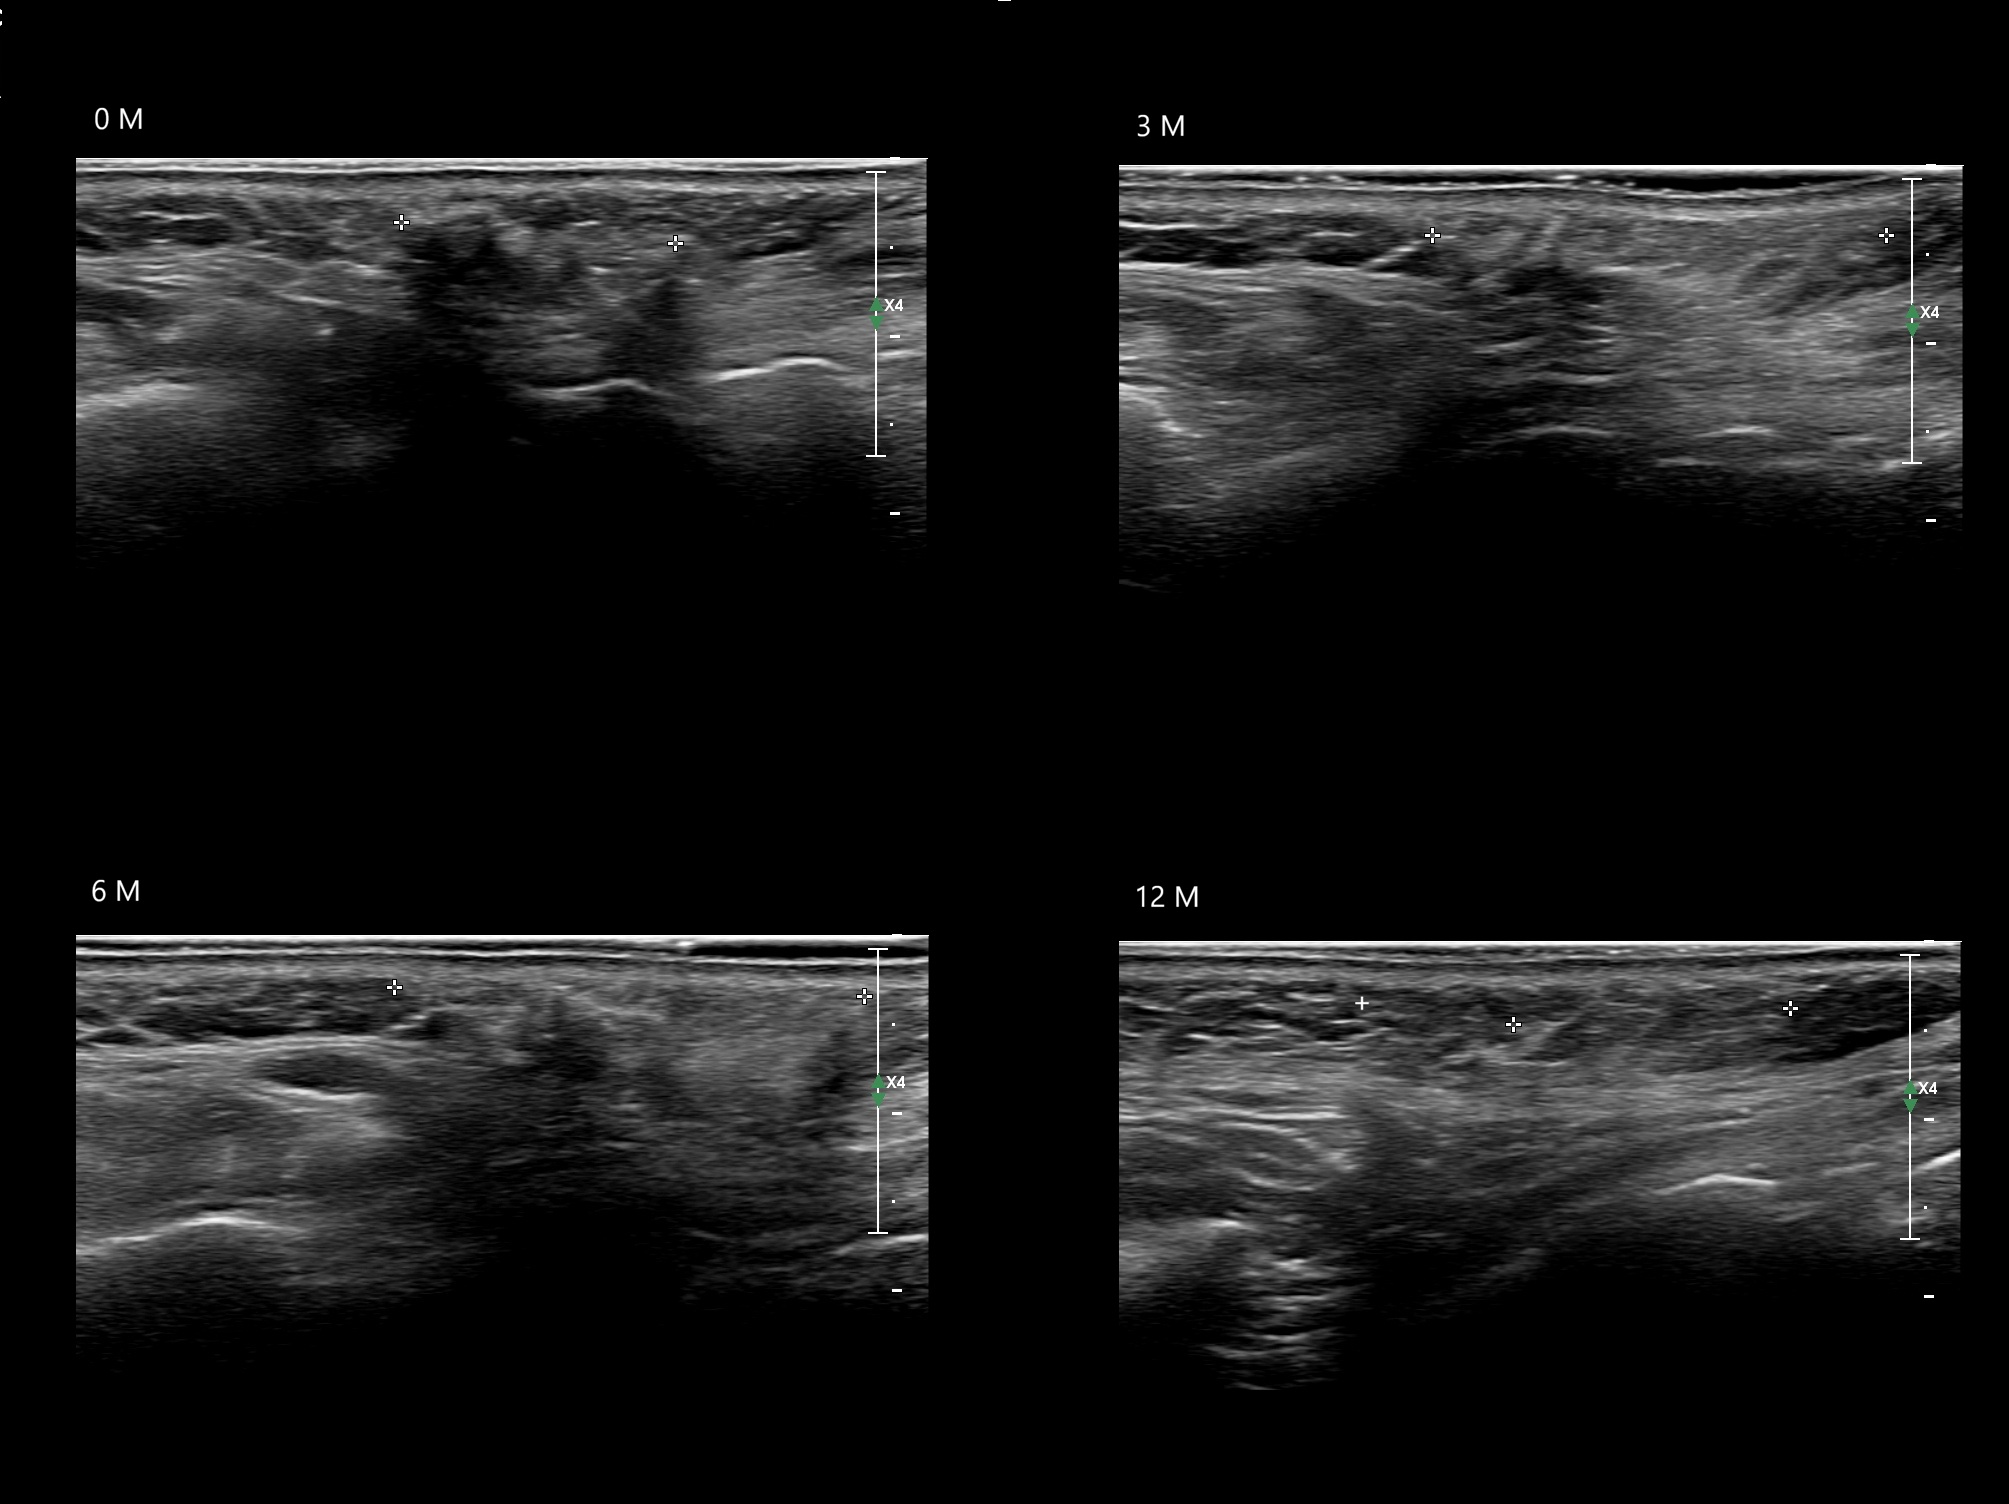

Draw in the image on the right where the fillers are located. To check if your answer is correct, please click on the secondary image.

Fillers

Draw in the second image below where the fillers are located. To check if your answer is correct, swipe the first image to the right.